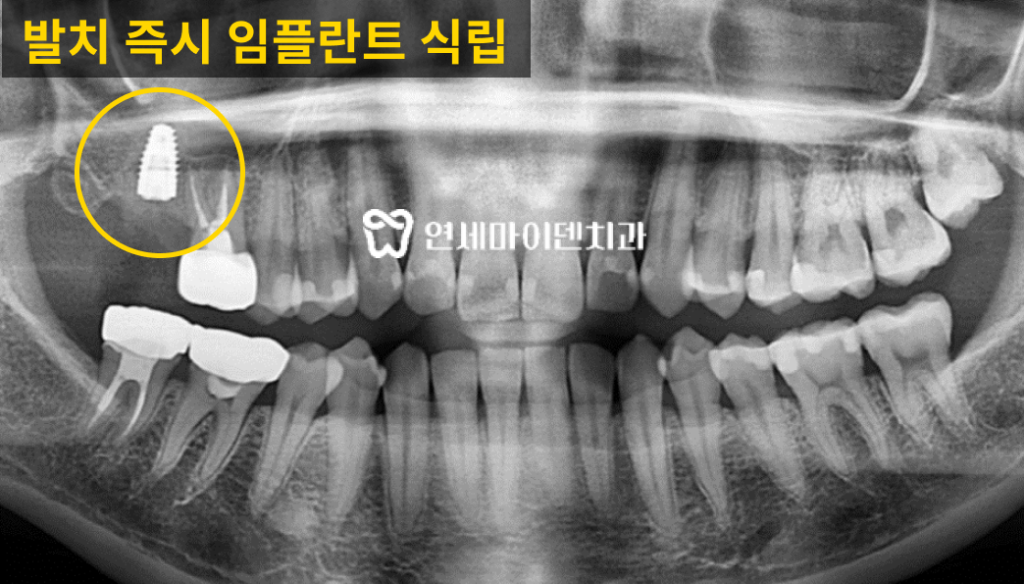

3D 네비게이션 CT를 기반으로

사전에 모의 수술을 통해 식립 위치를 설계하였습니다.이후 발치 즉시 임플란트를 시행하였고,

치아 발치 후 내부에 남아있는 염증 조직을 철저히 제거하였습니다.치조골이 부족한 부위에는 뼈 이식술을 병행하여

임플란트의 고정력을 확보하였습니다.

수술 2주 후 잇몸이 잘 아물고 있는 것을 확인했고,

3개월이 지난 시점에서 2차 수술과 함께

최종 보철물 제작을 진행하였습니다.발치 즉시 임플란트는 우리 신체의 치유 잠재력을

최대한 살릴 수 있는 방법이기 때문에발치 후 3개월만에 잇몸 뼈가 차오르고

임플란트 후 보철물까지 완성할 수 있었습니다.임플란트 성공률을 높이기 위해 확인해야 할 것